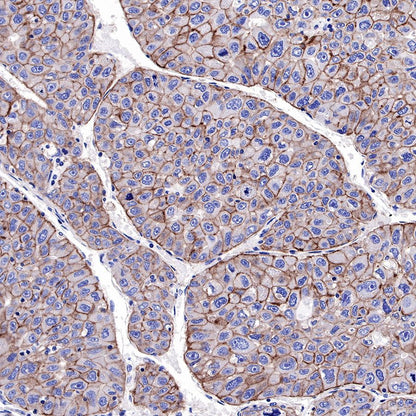

IHC shows positive staining in paraffin-embedded human hepatocellular carcinoma. Anti-EGFR antibody was used at 1/2000 dilution, followed by a HRP Polymer for Mouse & Rabbit IgG (ready to use). Counterstained with hematoxylin. Heat mediated antigen retrieval with Tris/EDTA buffer pH9.0 was performed before commencing with IHC staining protocol.